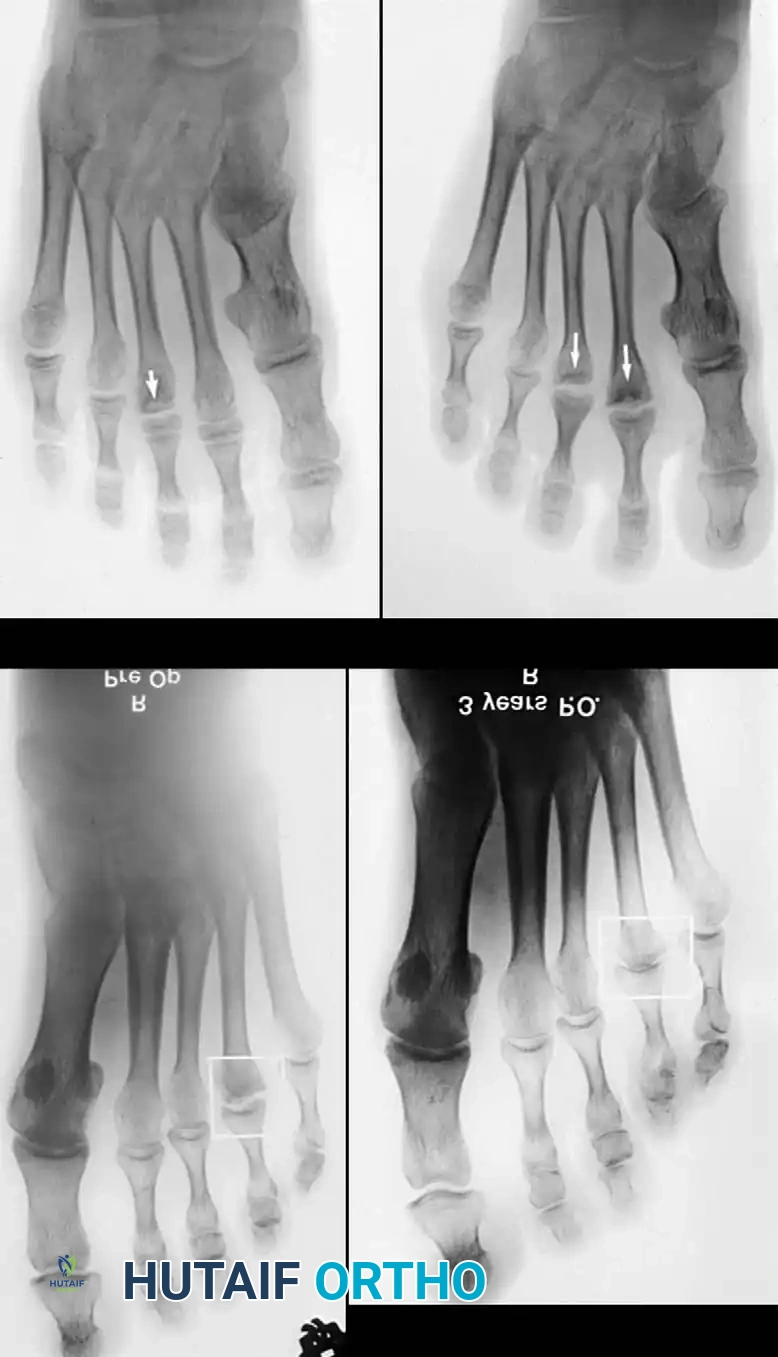

Weight-bearing anteroposterior (AP), lateral, and oblique radiographs of the foot are mandatory. Early radiographic findings may be subtle, showing only joint space widening due to effusion. As the disease progresses, classic signs emerge:

* Irregular ossification of the primary ossification center.

* Flattening and central depression of the metatarsal head.

* Widening and bicortical thickening of the metatarsal shaft.

* Osteochondral fragmentation and intra-articular loose bodies.

This extra-articular osteotomy is ideal for intermediate stages of Freiberg infraction where the necrotic lesion is localized strictly to the dorsal aspect of the metatarsal head, and the plantar articular cartilage remains healthy and viable. The goal is to rotate the healthy plantar cartilage dorsally to articulate with the proximal phalanx.